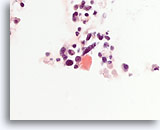

Afbeelding 16

Benigne, hyperplastisch/adenomatoïde nodule, schildklier FNA, celblok.

Dun colloïde linksonder vergeleken met het dichtere colloïde in de microfollikels pleit samen met het afgeplatte, atrofische uiterlijk van de folliculaire cellen in de microfollikels voor een benigne hyperplastische/adenomatoïde nodule.

40X

Afbeelding 16

Benigne, hyperplastisch/adenomatoïde nodule, schildklier FNA, celblok.

Dun colloïde linksonder vergeleken met het dichtere colloïde in de microfollikels pleit samen met het afgeplatte, atrofische uiterlijk van de folliculaire cellen in de microfollikels voor een benigne hyperplastische/adenomatoïde nodule.

40X